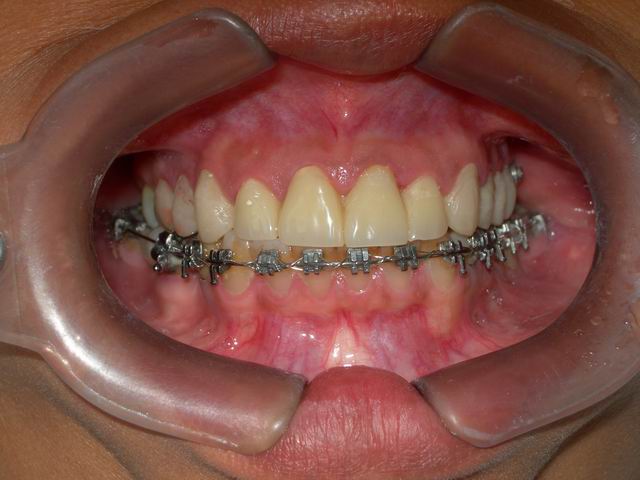

Tratamento ortodôntico prévio (vista frontal)

Caso concluído com próteses

metalocerâmicas cimentadas